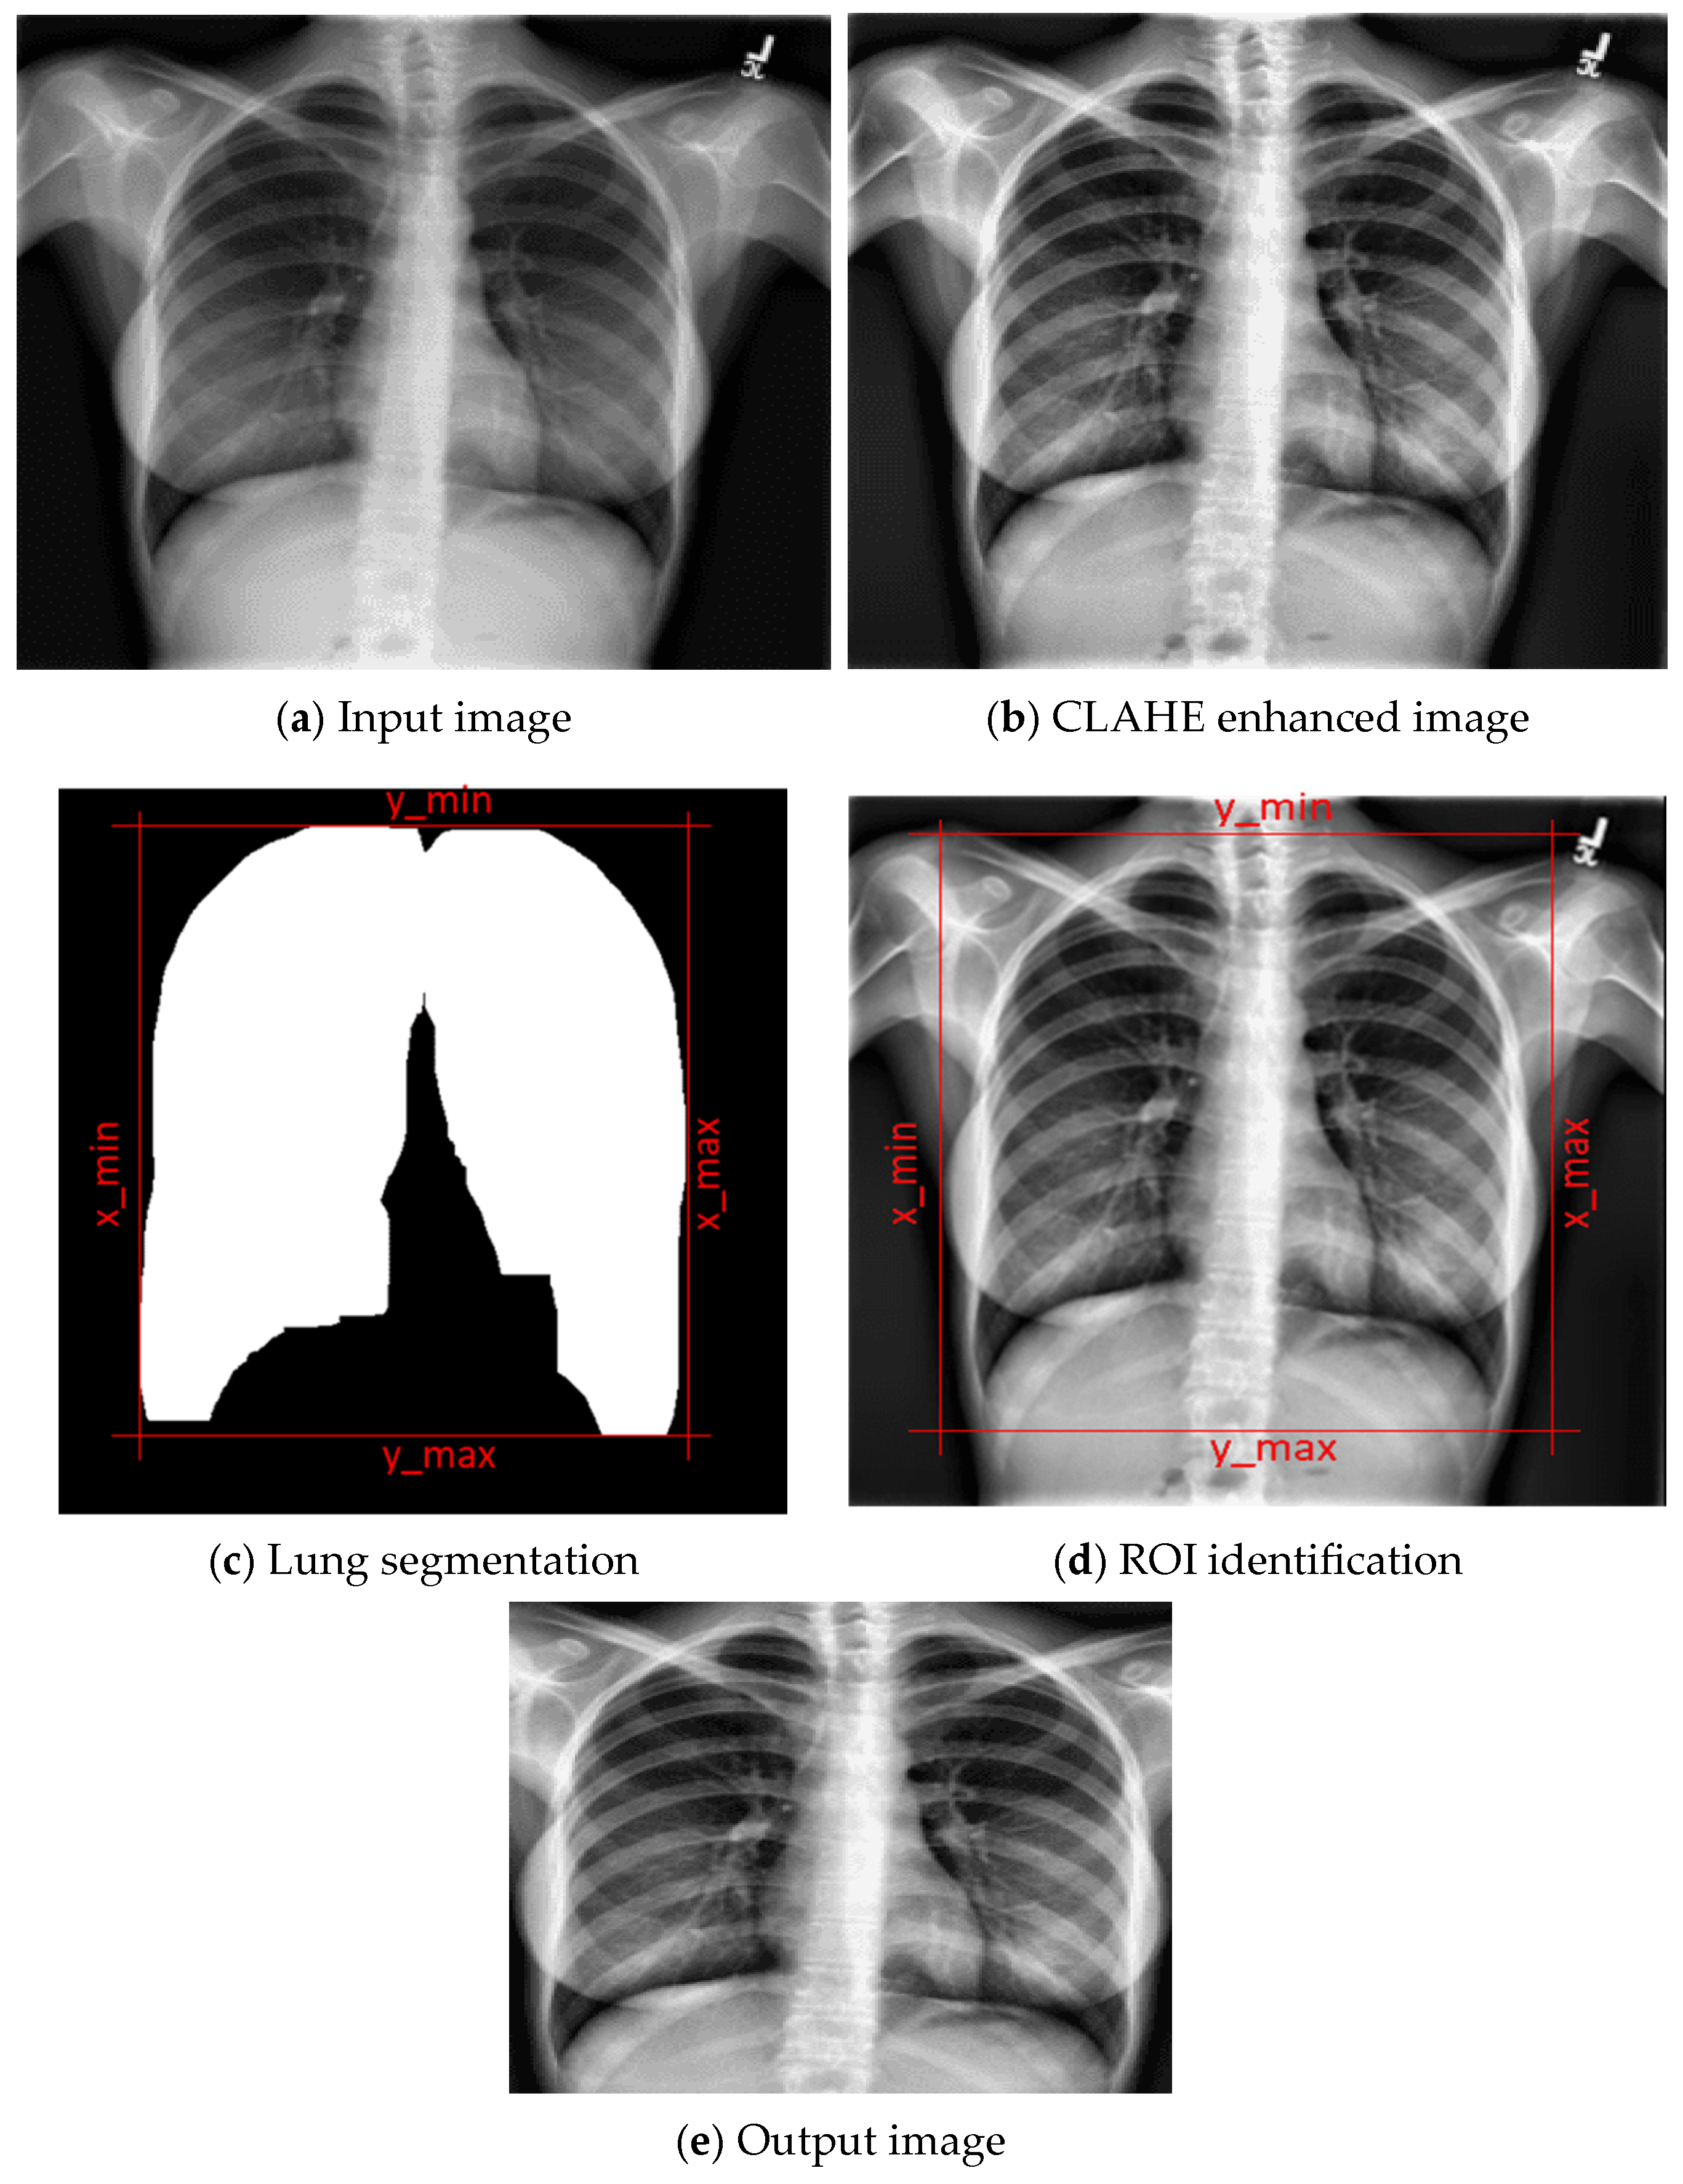

To enhance the diagnostic effectiveness of chest X-ray images, a series of preprocessing steps were applied. Publicly available datasets containing Normal, COVID-19, and Pneumonia cases were utilized, with preprocessing focused on improving image clarity and reducing noise. CLAHE was employed to highlight key structures such as lung textures and opacities, thereby improving visibility of clinically significant features. Segmentation was then performed to isolate the lung fields, ensuring that the model focused on relevant regions while excluding surrounding background areas. This process not only reduced false activations but also enhanced the accuracy of Grad-CAM heatmap generation by localizing the areas most responsible for prediction. To further increase robustness, the segmented images underwent data augmentation before training. Transformations such as random rotations, scaling, and brightness variations were applied to simulate real-world imaging variability. These augmentations strengthened the model’s ability to generalize across diverse clinical conditions and reduced overfitting.

CLAHE is an advanced image enhancement technique used to improve the contrast of images, particularly in medical imaging and low-contrast environments [47]. Unlike traditional histogram equalization that applies to a global contrast adjustment, CLAHE operates on small regions called tiles (usually 8 × 8 or 16 × 16 pixels), applying histogram equalization within each tile to enhance local details. To prevent noise amplification in nearly uniform regions, CLAHE introduces a contrast limiting step by clipping the histogram at a predefined threshold before redistributing the excess pixels. Mathematically, for a tile with intensity levels I(x, y), the transformation function T(i) is given by the cumulative distribution function (CDF) of the clipped and normalized histogram H(i):

T ( i ) = 1 M × N j = 0 i H c l i p p e d ( j )

where M × N is the number of pixels in the tile, and H c l i p p e d ( j ) is the clipped histogram count for gray level j. To avoid abrupt changes between tiles, CLAHE uses bilinear interpolation to merge neighboring tiles. This technique has proven effective in enhancing medical images such as MRI, CT, and ECG visualizations, by revealing subtle features while minimizing noise amplification.

According to the proposed framework, the preprocessing pipeline, as demonstrated in Figure 2, began with the application of CLAHE, which significantly improved local contrast and visibility of critical lung features. This enhancement is vital in radiographic imaging, where subtle opacities can indicate pathological changes. Following enhancement, the framework incorporated ROI identification to direct attention toward the lung areas, effectively minimizing background interference. Additionally, lung segmentation was performed to further isolate the anatomical zones of interest, ensuring that subsequent predictions and explanations pertain strictly to lung regions. This segmentation step also lays the groundwork for meaningful application of Grad-CAM visualizations.

Figure 2. Preprocessing steps with an image sample.